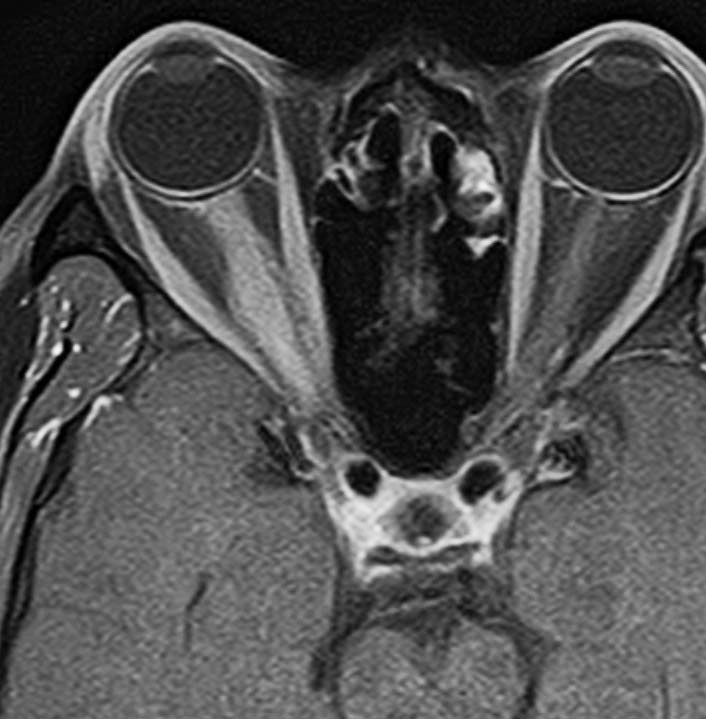

この図のように,視神経(黄色)は,骨(青色)で形成される視神経管の中を走行して頭蓋内へ入ります。視神経管は骨ですから,この狭い管の中に腫瘍が入ると視神経が腫瘍の圧迫でつぶれてしまって,視力障害を出しやすいです。

鞍結節髄膜腫(赤色)はこの視神経管の中に浸潤して伸びていく性質を有しています。ですから,視神経管の骨を削って,視神経管の中に潜り込んでいる腫瘍を根こそぎ摘出しないと,再発する可能性が高いです。